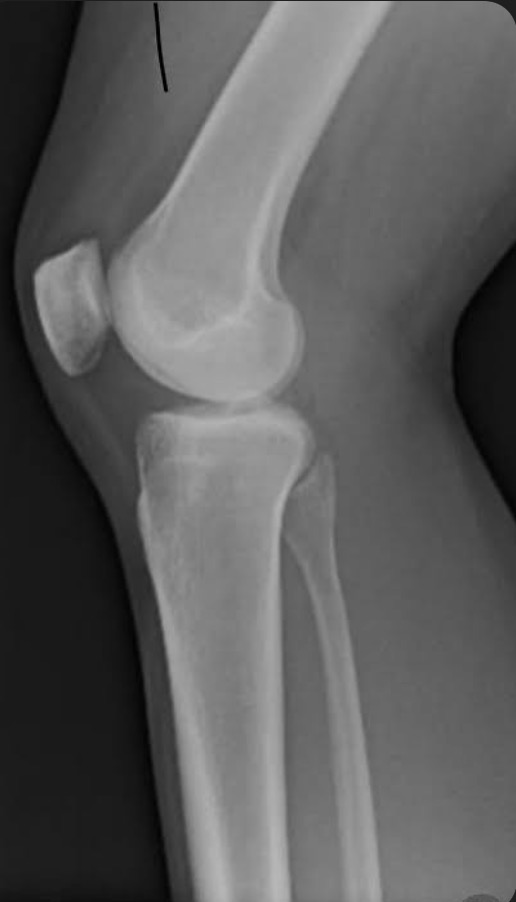

Name the projection.

Should it be repeated, if so why?

Lateral Knee

Yes. Patient is not in true lateral.

Fibular head and tibia are not superimposed.

Femoral condyles not superimposed

Label the image

A) Femur

B) Patella

C) Intercondylar eminence

D) Tibia

E) Fibular shaft

F) Fibular neck

G) Fibular head

H) Femorotibial joint

I) Femoral condyles